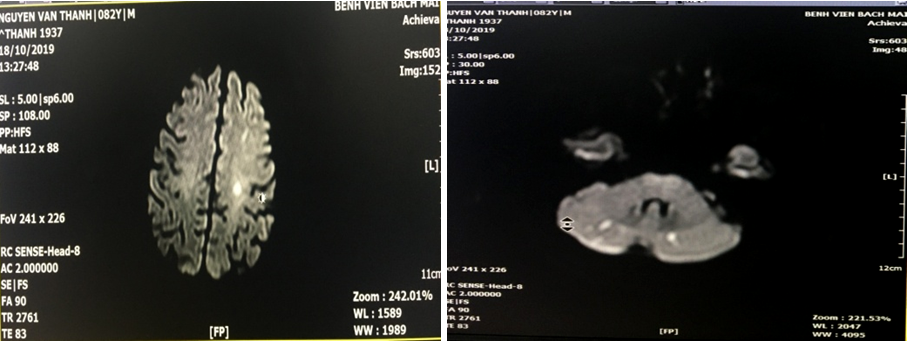

9. Kết quả chụp cộng hưởng từ ngực

Hình ảnh khối tổn thương kích thước 20x22mm kèm xơ hóa xung quanh thùy trên phổi phải. Tổn thương đông đặc nhu mô thùy dưới phổi trái. Dày tổ chức kẽ 2 phổi. Tràn dịch màng phổi 2 bên (phải: 27mm, trái: 28mm), tràn dịch màng tim (chỗ dày nhất 7mm). Hạch trung thất và rốn phổi phải. Không thấy huyết khối động mạch phổi.

Hình 1. Hình ảnh chụp cắt lớp vi tính lồng ngực

11. Cộng hưởng từ sọ não

Hình ảnh nhồi máu não thùy trán trái, thùy đỉnh phải và bán cầu tiểu não hai bên.

Hình 3. Hình ảnh cộng hưởng từ sọ não